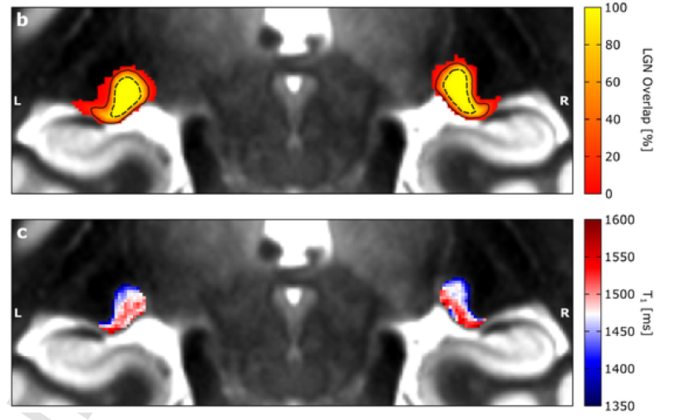

image: The upper panel shows the location of the visual sensory thalamus on high spatial resolution MRI data. The more yellow the colour the more participants have the visual sensory thalamus in this position. The lower panel indicates that information about the amount of white matter can be used to dissociate the two compartments of the visual thalamus. view more

The results showed that the two major compartments of the visual sensory thalamus are characterised by different amounts of brain white matter (myelin). This information can be detected in novel MRI data and thus, can be used to investigate the two compartments of the visual sensory thalamus in living humans.